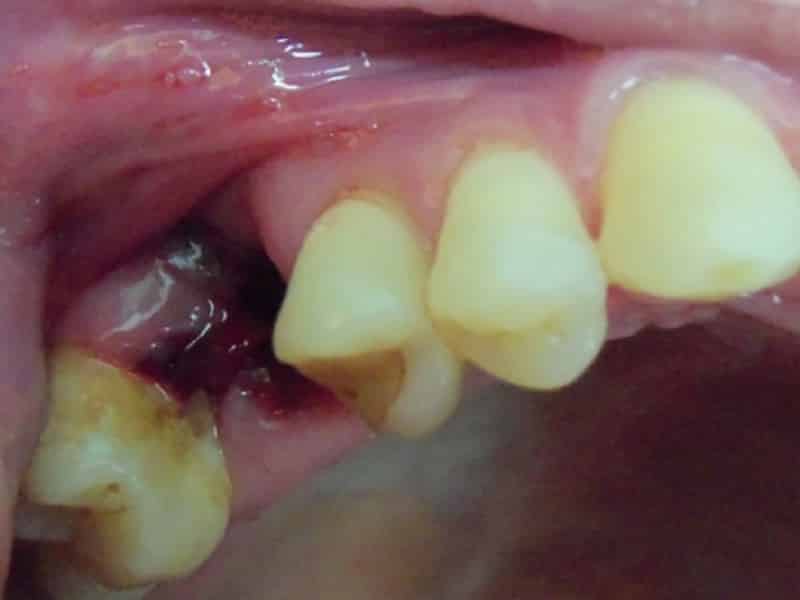

Что делать, если после удаления зуба лунка остается сухой (см. фото)? Какие могут быть причины этого явления и является ли это признаком альвеолита? Существует несколько ключевых факторов, способствующих развитию альвеолита в лунке:

- лунка выглядит пустой и сухой, отсутствует защитный кровяной сгусток, десна вокруг лунки сильно воспалена и вызывает боль при нажатии;

Если кровяной сгусток не образуется, то через несколько дней может возникнуть тупая ноющая боль, часто охватывающая одну из сторон челюсти. Обычно в лунке нет крови и гноя, что позволяет увидеть костную ткань.

Также стоит незамедлительно обратиться к врачу, если после удаления зуба сгусток выпал из лунки. Только стоматолог может правильно лечить альвеолит (см. фото). Задержка в обращении за медицинской помощью может привести к остеомиелиту и даже к серьезным последствиям.